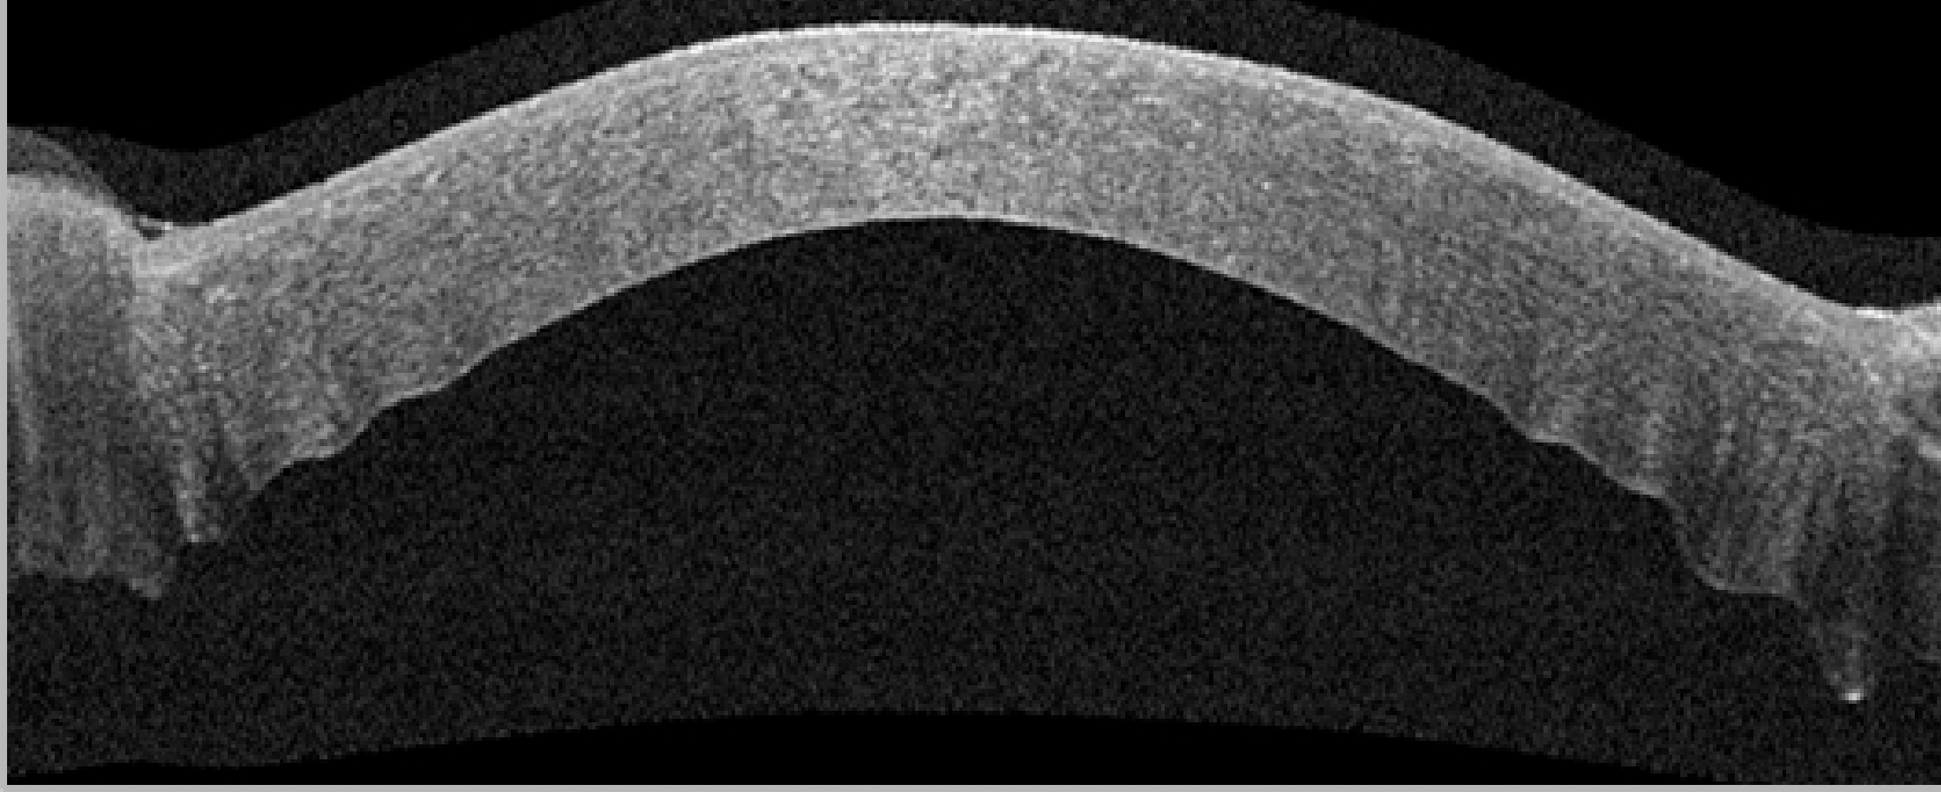

Говоря об анатомо-морфологических особенностях послеоперационных изменений роговицы в результате применения модифицированной методики ФРАК, следует отметить более равномерный задний профиль в центральной зоне роговицы на полученных снимках оптической когерентной томографии, отсутствие «складчатости» задней поверхности. Добавление обвивного шва в сравнении с ранее предложенной методикой ФРАК, где использовали узловые швы (рисунок 2), позволило обеспечить более равномерное натяжение роговичной ткани, тем самым не только избежать «волнистости» заднего профиля роговицы, но и уменьшить послеоперационный астигматизм (рисунок 3).

Рисунок 3. Скан ОКТ переднего отрезка глаза: равномерный задний профиль в центральной зоне роговицы (комбинированная шовная фиксация).

Figure 3. OCT scan of the anterior segment of the eye: uniform posterior profile in the central area of the cornea (combined suture fixation).

Наличие у всех пациентов, вошедших в исследование, выраженного фиброзирования в зоне выполненного в ходе ФРАК фемтолазерного реза свидетельствует об адекватной адаптации краев операционной раны. Комбинированная шовная фиксация позволила не только адекватно сопоставить края образовавшегося после фемторезекции канала, но и обеспечить максимально равномерное натяжение роговичной ткани, тем самым избежать изменений заднего профиля роговицы, а также уменьшить выраженность послеоперационного астигматизма.